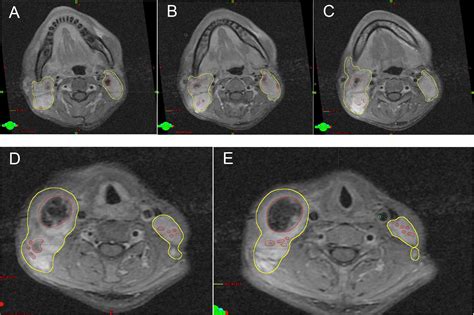

• Imaging Tests: Imaging tests, such as ultrasound, CT scan, or MRI, can help visualize the lymph nodes and detect any abnormalities.